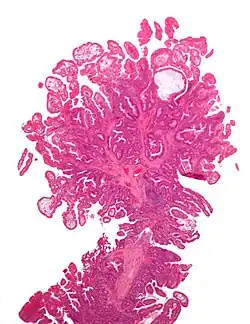

| Tubular adenoma | 2% at 1.5 cm[12] | Low to high grade dysplasia[13] | Over 75% of volume has tubular appearance.[14] |

| Tubulovillous adenoma | 20% to 25%[15] | 25–75% villous[14] |

| Villous adenoma | 15%[16] to 40%[15] | Over 75% villous[14] |

The common adenomas of the colon (colorectal adenoma) are the tubular, tubulovillous, villous, and sessile serrated (SSA).[18] A large majority (65–80%) are of the benign tubular type with 10–25% being tubulovillous, and villous being the most rare at 5–10%.[9]

The villous subdivision is associated with the highest malignant potential because they generally have the largest surface area. (This is because the villi are projections into the lumen and hence have a bigger surface area.) However, villous adenomas are no more likely than tubular or tubulovillous adenomas to become cancerous if their sizes are all the same.[18]

- Tubular adenoma: 5% risk of cancer

- Tubulovillous adenoma: 20% risk of cancer

- Villous adenoma: 40% risk of cancer

Micrograph of a villous adenoma. These polyps are considered to have a high risk of malignant transformation. H&E stain. -